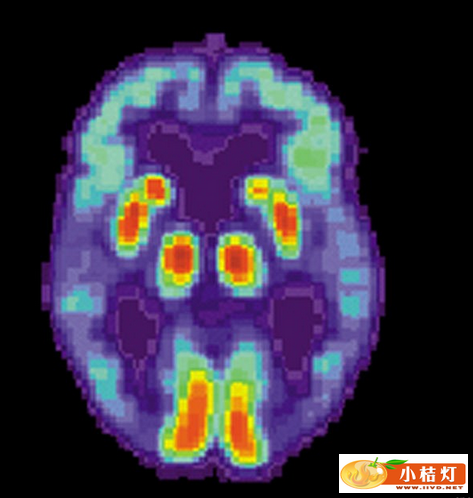

阿尔茨海默症患者大脑的PET扫描图

针对40位试验对象的初步研究数据显示,视网膜的淀粉样蛋白水平与正电子发射断层摄影术(PET)扫描显示的大脑淀粉样蛋白含量水平呈现密切相关性,PET是目前所使用的阿尔茨海默症检测方法。